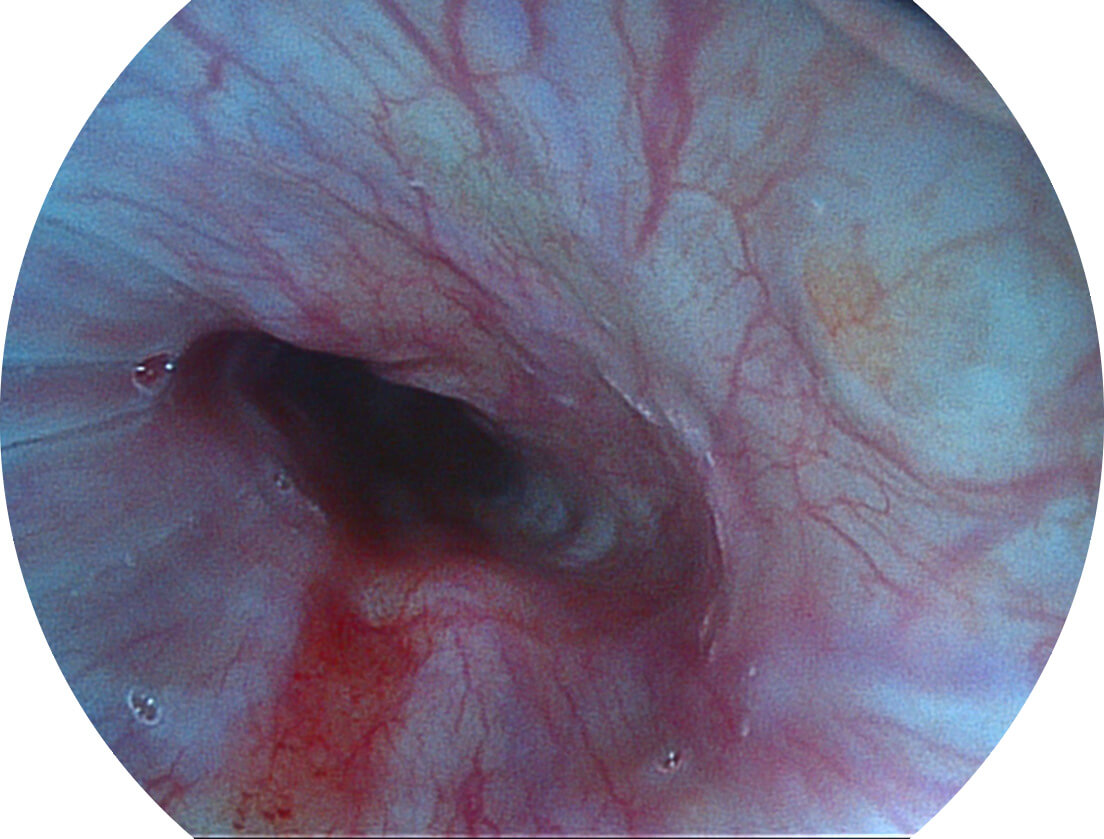

白光图像

VIST图像

采用光路合束技术,光谱自由度高,实现了更丰富的照明模式,染色模式SFI及VIST,从远景到近景,助力消化道早期疾病诊断。